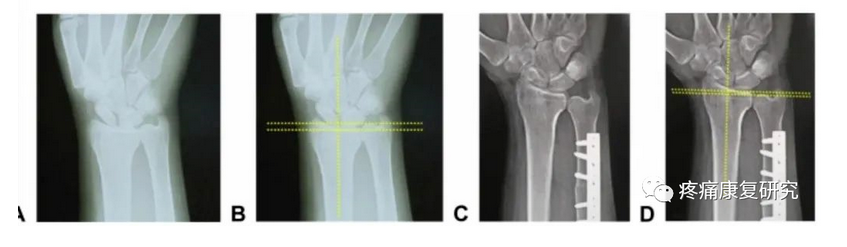

1.尺骨短缩截骨术 (USO)

这是治疗 UIS 的经典术式,适用于各种尺骨阳性变异的 UIS 患者。

USO 是一种关节外手术,不会损伤关节内组织,但同时也无法直接修复关节内损伤,但 USO 降低尺骨长度后,能下拉收紧三角纤维软骨复合体(TFCC),增加其张力,降低尺腕关节负荷,治疗合并TFCC撕裂的UIS可取得良好的临床效果。

尺骨撞击综合征患者行尺骨短缩截骨术术前术后X线片

目前 USO 截骨部位有尺骨干截骨和干骺端截骨,钢板安置部位有掌侧和背侧,截骨方式有徒手截骨和专用工具引导下截骨,截骨形状有横形、斜形、梯形等,其中徒手截骨和横行截骨因操作简便而应用较广。